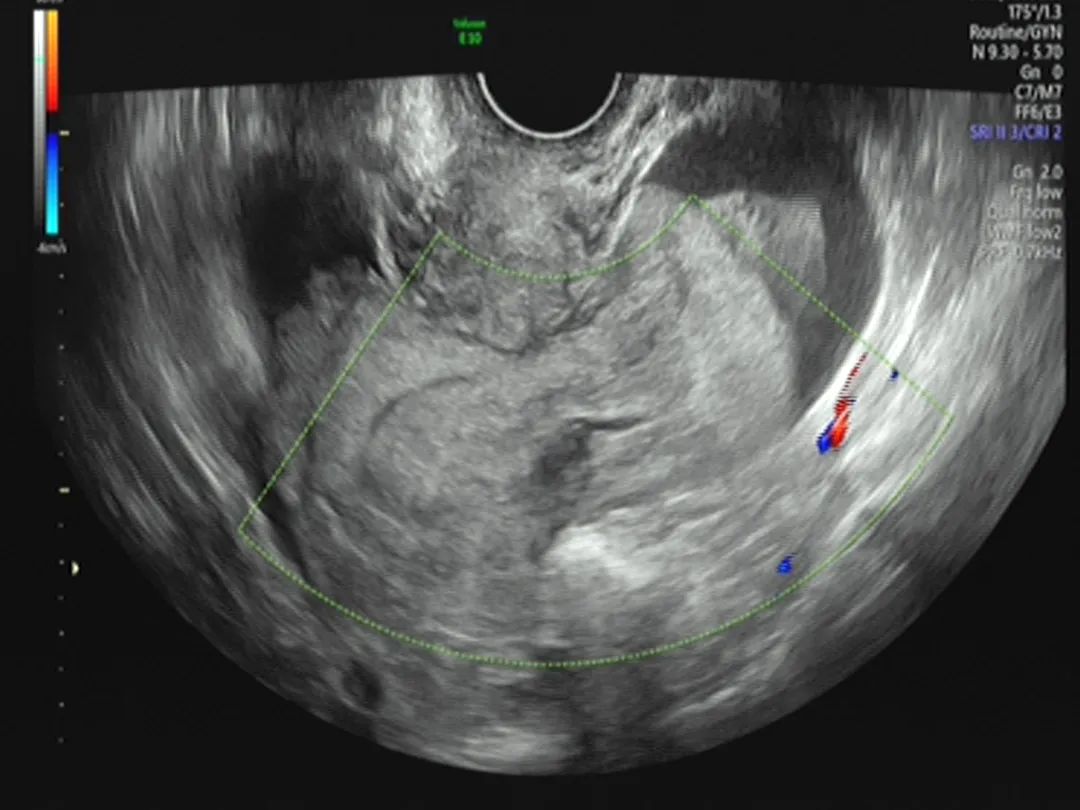

葛静主任见到患者后,根据经验判断患者很可能出现了腹腔内大出血,决定马上启动应急预案,组织团队进行救援。赵红艳护士长带领护理团队紧张有序地完成了输血、补液、导尿、心电监护等必要环节;葛静主任技术娴熟地进行后穹隆穿刺,发现有明显出血,这也验证了她的判断,超声显示腹腔内出血量大,已经看不到出血点;尿液样本送到检验科1分钟后,就出了结果——HCG阳性。

超声显示腹腔内有大面积出血